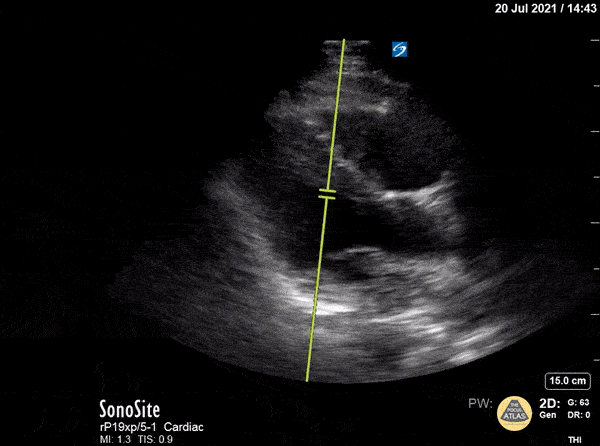

Right Ventricular Dysfunction - McConnell's Sign on PLAX View

RV dilation violating the rule of thirds. McConnell’s sign is also demonstrated in this view with RV apical hyperkinesis and lateral wall hypo/akinesis. Patient was found to have a submassive pulmonary embolism. Moudi Hubeishy @hubeishy_MD